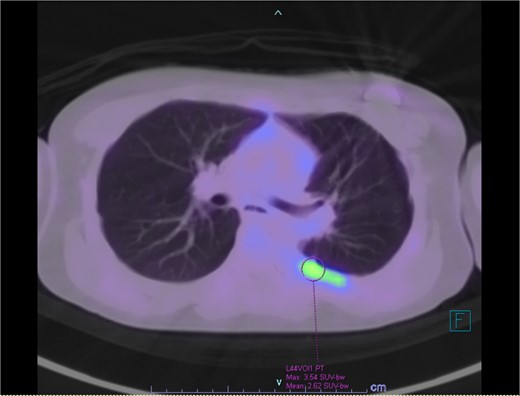

Our patient is a 10-year-old Caucasian female with a history of early adrenarche, ADHD, and COVID-19 and no past surgical history. She presented to the ED with a month-long history of persistent coughing, shortness of breath on exertion and speaking, and left-sided chest pain that began after a diagnosis of mildly symptomatic COVID-19. A physical exam revealed decreased breath sounds on the left, with a left-sided chest protrusion. A plain film and CT demonstrated a normal right lung, with a significant mediastinal shift toward the right, displacement of the heart into the right hemithorax, with complete whiteout of the left hemithorax, and demonstrating a mix of solid and cystic foci, with a round opacification at the left lung base (Figs 1 and 2). The patient underwent an uncomplicated left thoracotomy with excision of two masses, one being 22.5 × 21.0 × 10.5 cm and the other being 13.5 × 11.5 × 6.2 cm. These masses weighed 2394 g in aggregate. The specimens consisted of well-encapsulated tumors attached to the posterior aspect of the chest wall. A regional, positive lymph node measuring 3.0 × 2.2 × 1.0 cm was also resected. Due to the large size of the tumor and the requirement for clean margins, parts of the latissimus dorsi and serratus anterior muscles were also resected. By postoperative day (POD) 0, the left lung had already filled the left hemithorax, and the mediastinal shift had corrected (Fig. 3). The chest tube was removed on POD 5, and a plain film showed continued expansion of the lung to full size and resolving pulmonary edema and atelectasis (Fig. 4). The patient was discharged home on POD 5. The tumor staging was T4N1M0. The tumor was positive for vimentin, CD56, synaptophysin, chromogranin, and NSE. The tumor was negative for pancytokeratin, Cam5.2, EMA, S100, desmin, SMA, SOX10, HMB45, CD117, DOG1, CD99, PR, CD68, WT1, CD30, p53, Alk1, GFAP, and nuclear β-catenin. Next-generation sequencing showed an MGA:NUTM1 fusion, supporting a final diagnosis of high-grade MGA:NUTM1 fusion SCS. Given the size and grading of the tumor, the patient underwent adjuvant CT-RT with ifosfamide, doxorubicin, and proton beam radiotherapy, with supportive doses of MESNA and dexrazoxane for 4.5 months post-operatively. The basis of this treatment is ARST0332 Arm C [6]. Before treatment initiation, the patient underwent an uncomplicated left oophorectomy for reproductive cryopreservation. A PET/CT prior to CT-RT showed hypermetabolic activity in several areas. These included the pleural resection margin, a mediastinal lymph node concerning for metastasis versus postsurgical change, and a left axillary lymph node concerning for metastatic disease. During treatment, the patient contracted human metapneumovirus and rhino/enterovirus, resulting in febrile neutropenia. The patient was successfully treated with blood and platelet transfusions and pegfilgrastim. Upon completion of CT-RT, PET/CT imaging showed no evidence of residual disease, with minimal focal hypermetabolic activity as compared to the previous imaging (Fig. 5).

PET/CT showing residual hypermetabolic focus at plural resection margin, concerning for residual disease.